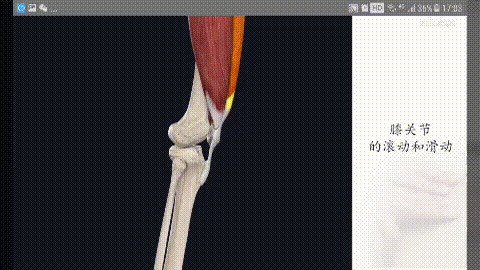

膝関節は体重のかかり方に特徴があり、社会活動やスポーツをする際にその負担は大きくなる。 膝関節が柔軟であり、かつ大きな負荷に耐えるためには、周囲の筋肉の複雑な構造がカギとなる。膝の冷えや痛み、ポキポキは、膝関節の構造で十分説明できます。

膝関節の伸展構造

私たちは二本の脚を頼りに歩いているのだから、膝関節を伸ばして重心を移動させなければならない。膝は後方に曲げることができるが、膝関節の安定性を維持するために、前方や側方への可動性は原則的にない。この安定性を維持するための基本は、膝関節に不可欠な4つの要素にある:

(i)動力源としての大腿四頭筋、(ii)膝蓋骨、(iii)膝蓋腱、(iv)脛骨結節からの作用点。

伸展時および収縮時に膝関節がガタつく。

膝を伸ばすと、膝蓋骨は膝関節の屈曲と伸展に伴って動いていることがわかります。膝蓋骨の下には、いわゆる膝蓋下脂肪体があり、膝関節伸展の構造上重要な部分です。膝蓋下脂肪体は、膝関節伸展運動のクッション効果を持ち、膝関節伸展運動を円滑な構造に保つ働きがあります。

一般的に、このような構造は、膝関節を繰り返し使う中で摩耗や損傷を引き起こし、膝関節の動きに何らかの影響を与えることになり、動作時のガタつきはその表れのひとつと考えられる。

また、関節が動くとガタつく原因として、関節面の過度の摩耗というものもあります。 私たちの膝関節は、関節面が滑らかに動くように細かい滑らかな軟骨で覆われているのですが、ケガや使いすぎなどで摩耗が進むと、関節面が凸凹になり、関節が動くときにその凸凹の上を骨が滑ってガタつくのです。関節が動くと、骨が凸凹の関節面を滑ってガタが生じ、激しい痛みを伴います。